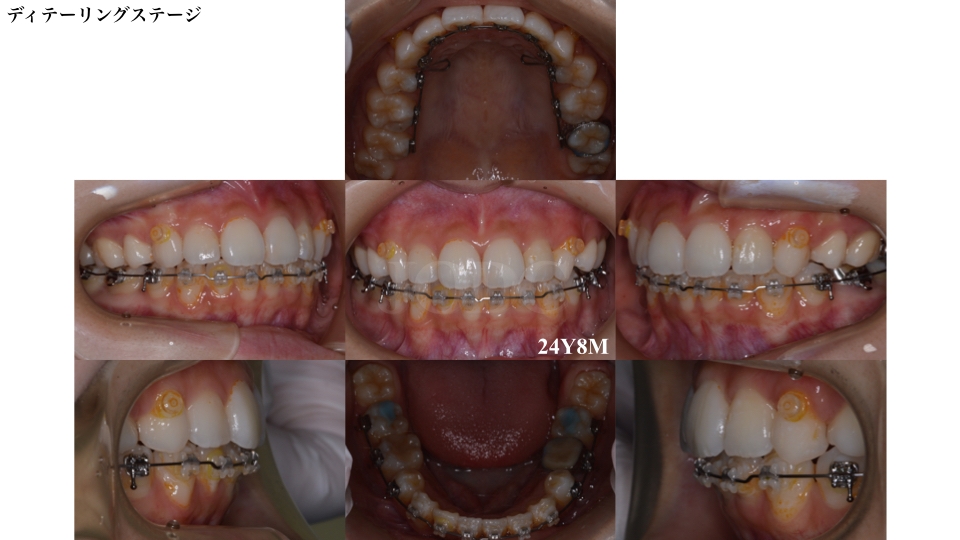

個々の歯の詳細な配列を行うディテーリングステージです。